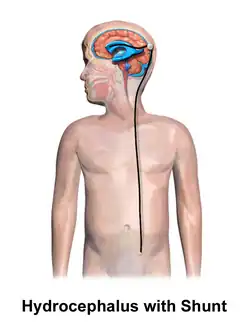

Hydrocephalus is typically treated through surgery. One option is the placement of a shunt system.[1] A procedure called an endoscopic third ventriculostomy has gained popularity in recent decades, and is an option in certain populations.[4] Outcomes are variable, but many people with shunts live normal lives.[1] However, there are many potential complications, including infection or breakage.[4] There is a high risk of shunt failure in children especially.[4] However, without treatment, permanent disability or death may occur.[1]

.jpg)

Hydrocephalus is treated through surgery by creating a way for the excess fluid to drain away. An external ventricular drain (EVD), also known as an extraventricular drain or ventriculostomy, provides relief in the short term.[48] In the long term, some people will need any of the various types of cerebral shunts.[48] It involves the placement of a ventricular catheter (a tube made of silastic) into the cerebral ventricles. This creates a way to bypass the flow obstruction/malfunctioning arachnoidal granulations. The excess fluid drains into other body cavities where it can be resorbed. Most shunts drain the fluid into the peritoneal cavity (ventriculoperitoneal shunt).[49] Other shunts drain the fluid into the right atrium (ventriculoatrial shunt), pleural cavity (ventriculopleural shunt), and gallbladder.[49]

A shunt system can also be placed in the lumbar space of the spine. This allows the excess fluid to be redirected to the peritoneal cavity (lumbar-peritoneal shunt).[50] Another treatment for obstructive hydrocephalus is an endoscopic third ventriculostomy (ETV). This surgery creates an opening in the floor of the third ventricle so that CSF flows directly to the basal cisterns. This treatment can shortcut any obstruction like aqueductal stenosis. This may or may not be appropriate based on individual anatomy. Some infants can be treated with ETV and choroid plexus cauterization.[51][52] Choroid plexus cauterization reduces the amount of cerebrospinal fluid produced by the brain. The technique, known as ETV/CPC, was pioneered in Uganda by neurosurgeon Benjamin Warf and is now in use in several U.S. hospitals.[51][52]